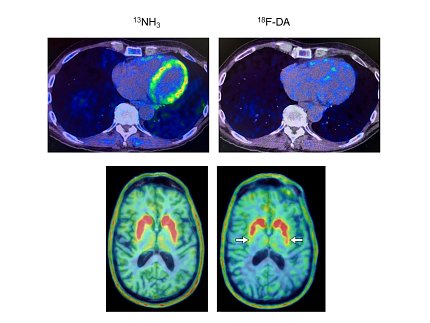

Heart PET scans from a study participant who developed Parkinson’s disease. The scan at right shows low dopamine-derived radioactivity, which appeared before symptom onset.

Photo:  GOLDSTEIN LAB/NINDS

Of nine individuals with low cardiac 18F-dopamine-derived radioactivity at their first scan, eight were diagnosed later with Parkinson’s or Lewy body dementia. Only 1 of 11 participants with normal initial radioactivity developed a central Lewy body disease. All nine participants who developed Lewy body disease had low radioactivity before or at the time of diagnosis.

“We think that in many cases of Parkinson’s and dementia with Lewy bodies the disease processes don’t actually begin in the brain,” said NINDS Principal Investigator Dr. David Goldstein. “The loss of norepinephrine in the heart predicts and precedes the loss of dopamine in the brain in Lewy body diseases…If you could salvage the dopamine terminals that are sick but not yet dead, then you might be able to prolong the time before the person shows symptoms.”